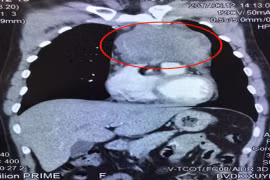

Chiều 17-6, Bệnh viện Đa khoa Xuyên Á (BVXA) thông tin đã phẫu thuật thành công cắt khối u trung thất (u ở phần lồng ngực giữa hai lá phổi) kích thước rất lớn 13x15x18 cm.